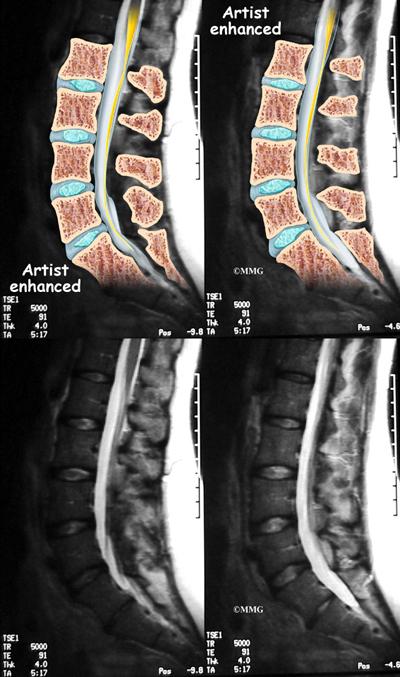

Diagnosis is based on a combination of a patient’s symptoms, physical examination, blood tests, and imaging studies such as X-rays or MRI.

Typically, doctors will first evaluate your symptoms and medical history. Blood tests can check for inflammation and the presence of HLA-B27, a genetic marker. Imaging tests like X-rays or MRIs can help visualize the affected joint and check for signs of inflammation and damage.